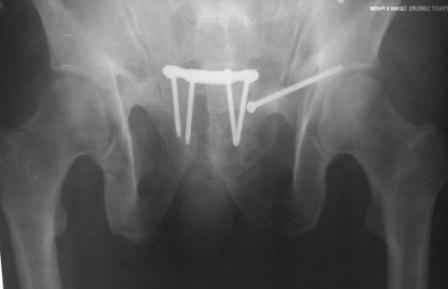

положение и точка введения винта, при фиксации перелома горизонтальной ветви лонной кости и возможно acetabulum, определяется её анатомией. Корректная позиция и точка введения в приложенных картинках из руководства по внутреннему остеосинтезу.

С Уважением А.Миронов

1.jpg

64KB (66029 bytes)